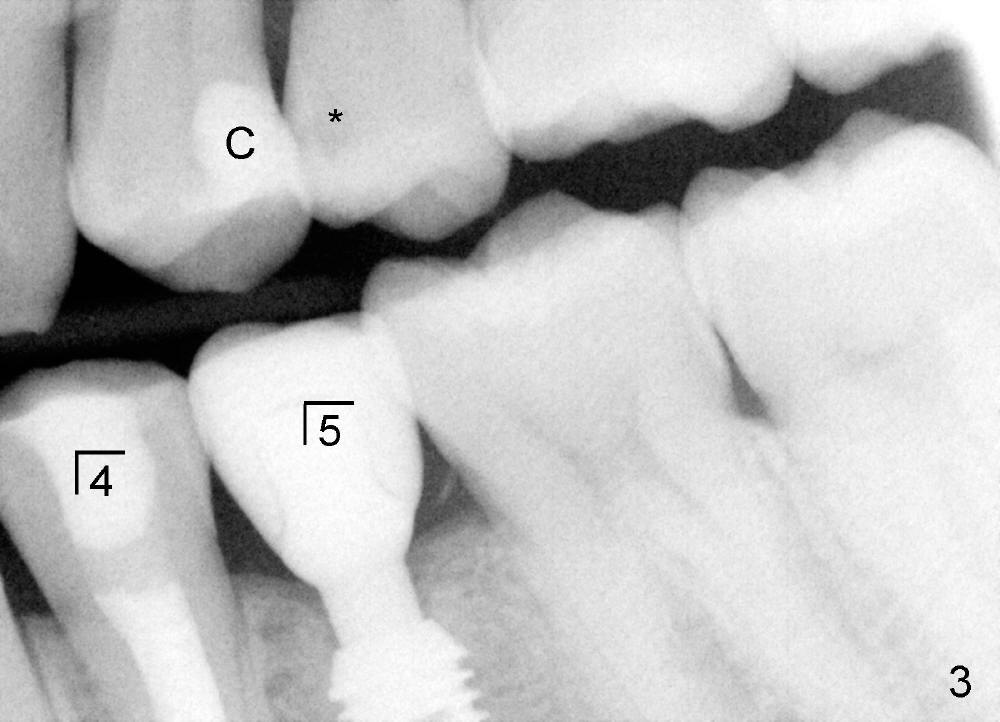

五年前,小许二十出头,四个下颌双尖牙中央牙尖畸形,左下第二双尖牙(图一:5)好像没有症状,但挺难保留,拔除后三个月植牙(delayed vs. immediate,这治疗(delayed implantation)合适吗?),图二是牙冠(C)戴上后半年拍摄的,A:基牙,I:Bicon植牙(5x8 mm,太短吗?)。虽然第一双尖牙也没有症状(图一:4),植牙前,重做根管治疗(图二:R,过分治疗吗?),使用flowable(*)和packabe(B)树脂关闭根管治疗开口,选择不做牙冠(治疗不足?)。

之后病人到外州读研究生,偶尔回来洗牙,图三是治疗完毕后一年半拍摄的,可能是为了诊治上颌双尖牙龋齿(*)和树脂(C)。半年前他回城看望父母,有点不适,但是没空来诊所。昨天他终于回来,问题不轻,你们能猜到是那个上面提及over- or under-treatment造成的?